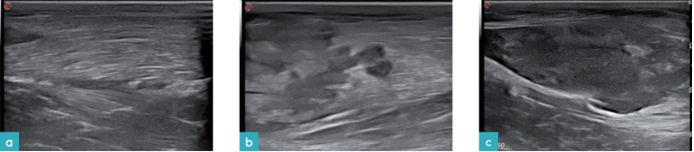

肌肉肿瘤可为固体,囊状,或为两种形式混合的结构。肿瘤的回声常是混合形式的,从无回声到高回声均有可能,均质或非均质的质地(图12)。可见或不可见肿瘤的边界。若想将机化的血肿,脓肿和肿瘤区分,就需要进行细针抽吸或活检检查。